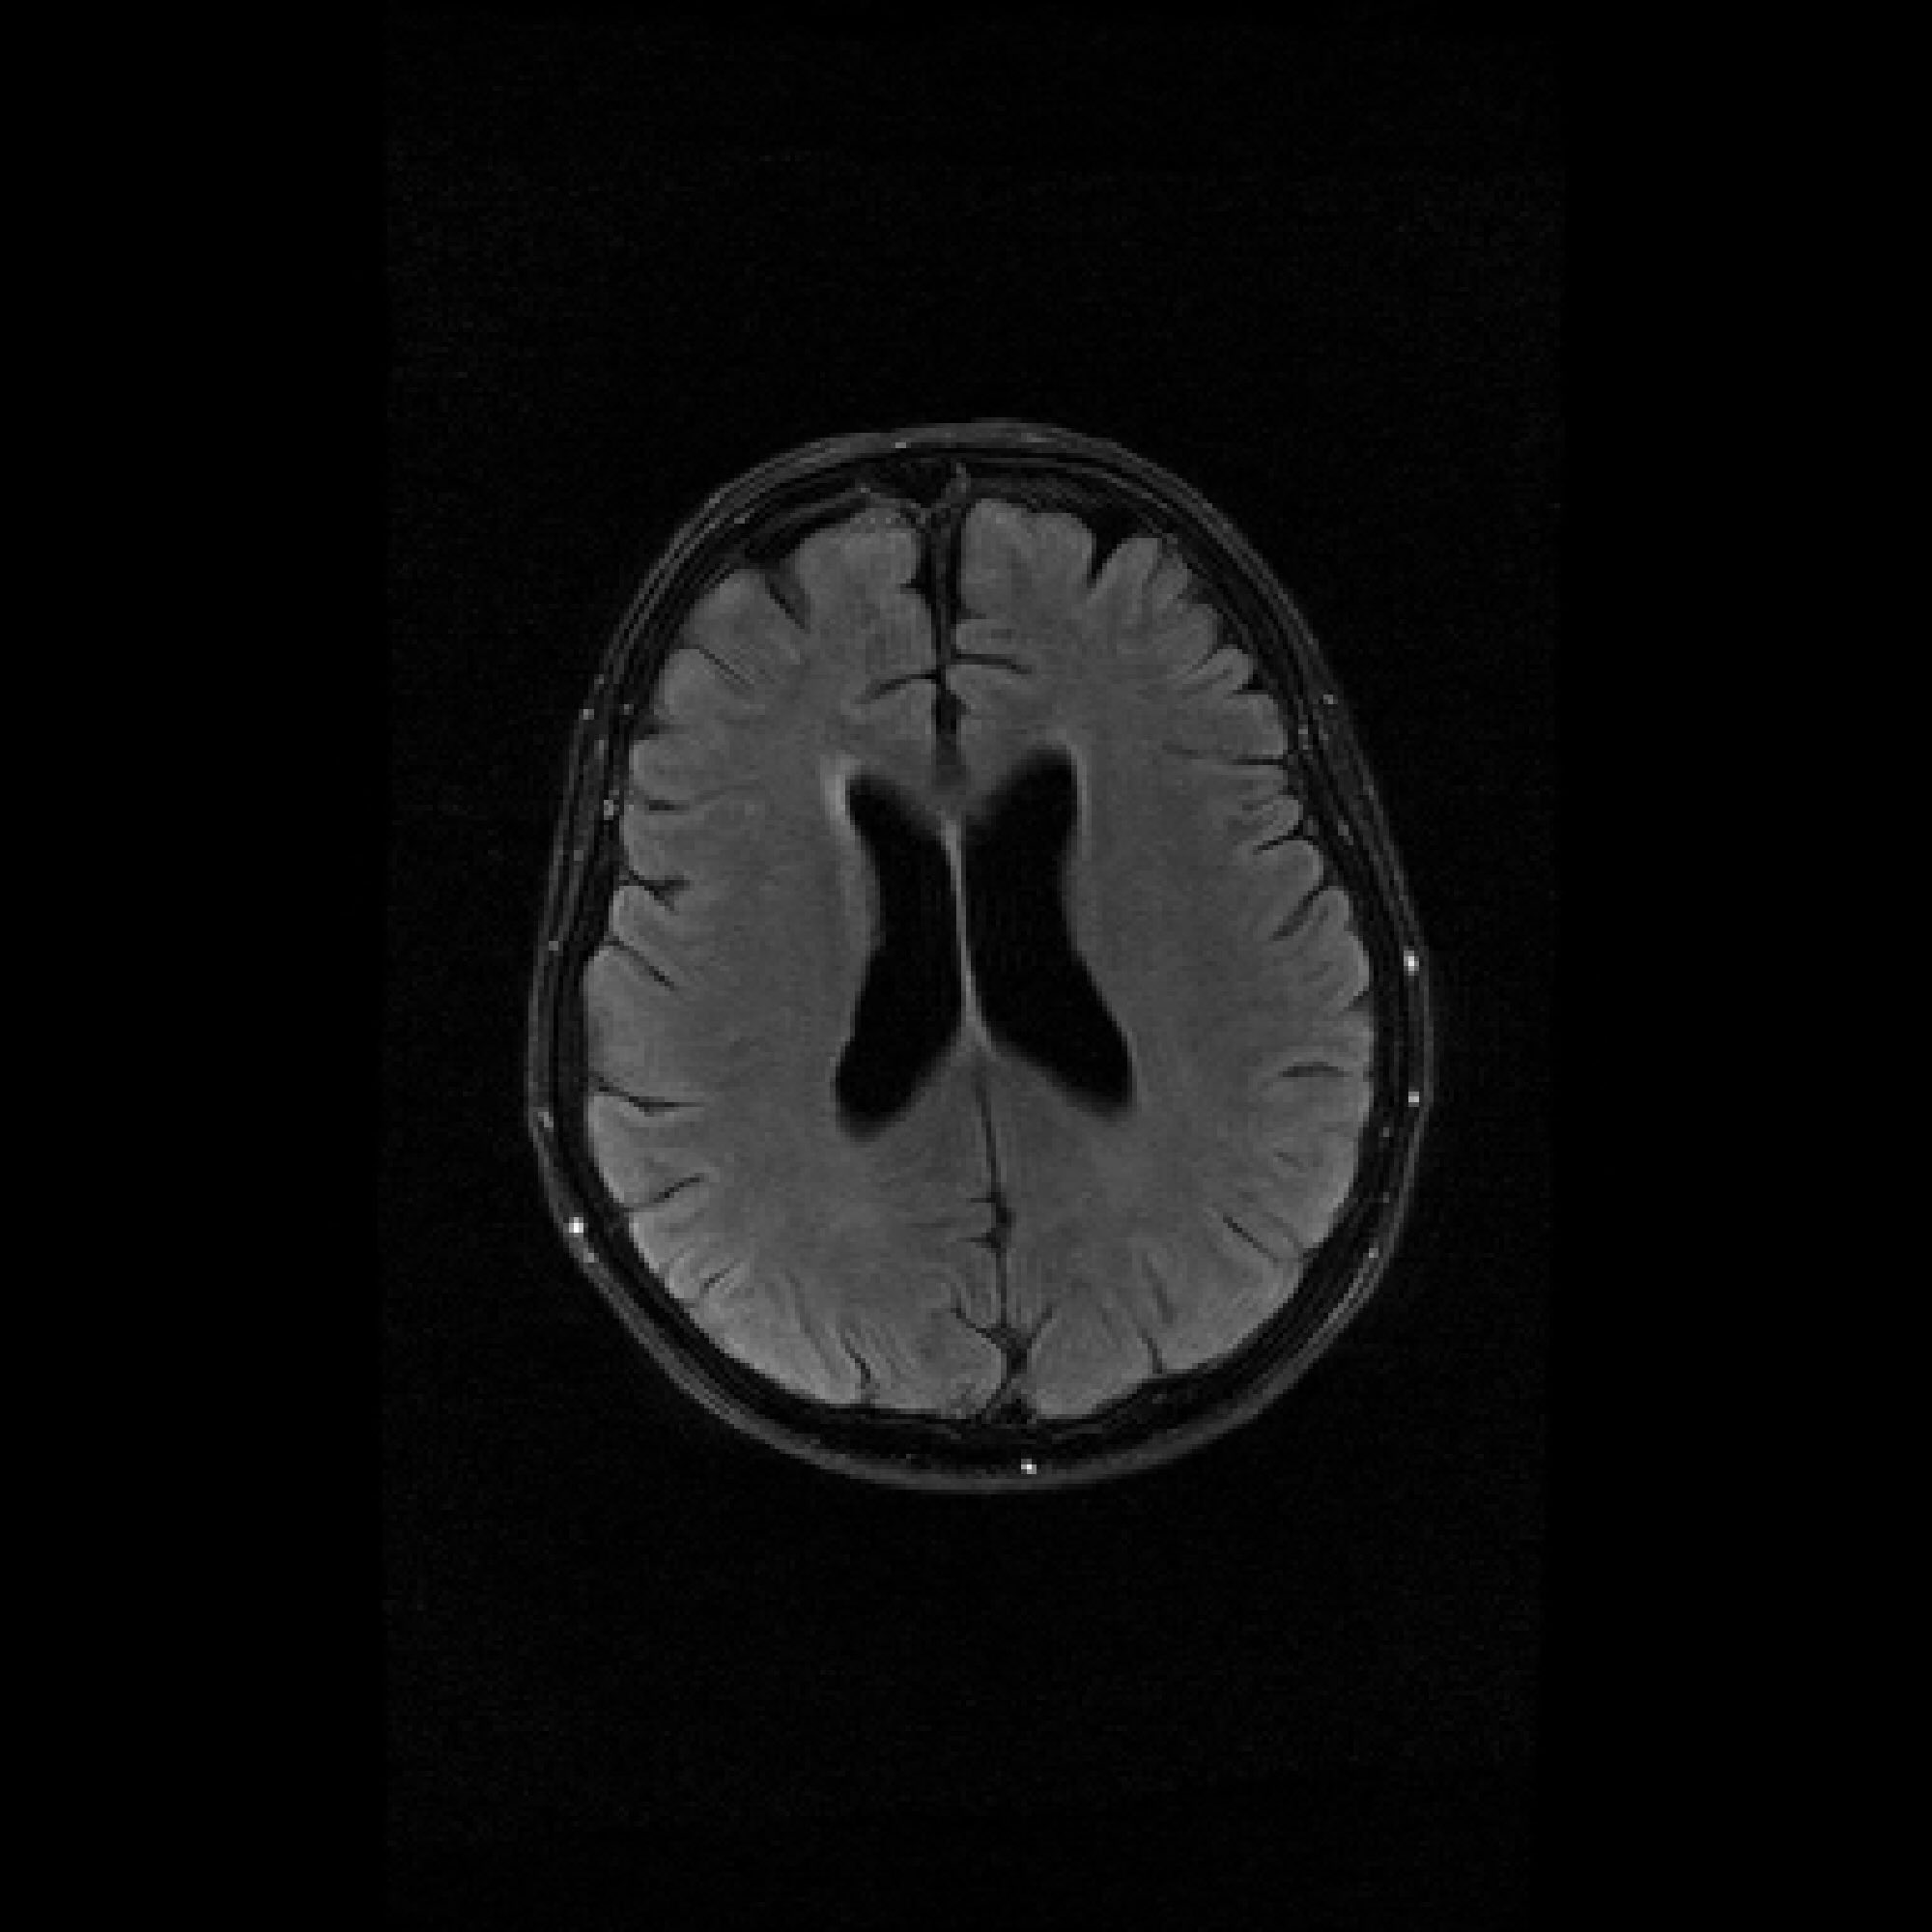

Refer to caption

Figure 3: Pixel-wise standard deviations of reconstructions across 10 random k-space sampling masks (R=7R=7) of the same slice. Top to Bottom: models trained on 100, 500, and 1000 slices. PaDIS-MRI consistently exhibits lower pixel-wise variance (fewer bright regions) than FastMRI-EDM across training sizes and contrast types, indicating more stable reconstruction.

Figure 3 visualizes these standard deviation maps, with brighter regions indicating higher variability between reconstructions. Across the 100-slice, 500-slice, and 1000-slice training regimes, PaDIS-MRI exhibits noticeably lower uncertainty compared to FastMRI-EDM, with the largest differences occurring at the smaller training dataset sizes. This suggests that decomposing the reconstruction problem into localized patches enables more stable learning of anatomical features, resulting in more reliable and consistent predictions from limited training data.

Table 1 quantifies these observations over our evaluation dataset. Due to computational costs of reconstructing each validation image across 10 random seeds, we randomly subsample a smaller evaluation set of 17 images (10 T2-axial, 5 T1-axial, 2 FLAIR) that preserves the contrast-type distribution of the training dataset. We crop each image to its original 384×320384\times 320 dimension to ignore deviations in our zero-padded regions, and report the pixel-wise standard deviation averaged across all test images. Again, PaDIS-MRI consistently achieves lower standard deviation values than FastMRI-EDM on average, with differences being most pronounced at smaller dataset sizes. These results further strengthen the case for patch-based diffusion priors in data-scarce settings. A breakdown of uncertainty averages by contrast type can be found in Appendix C.2.